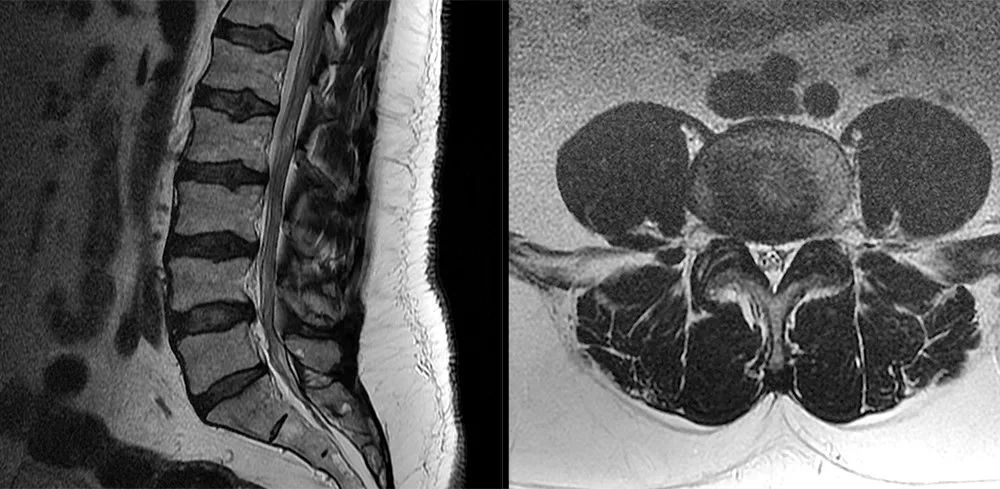

• 椎管内硬膜外脂肪增多症与终丝脂肪沉积

• 常见易忽略的疾病—椎管内硬膜外脂肪增多症

常见易忽略的疾病—椎管内硬膜外脂肪增多症

• 椎管内硬膜外脂肪增多症

椎管内硬膜外脂肪增多症